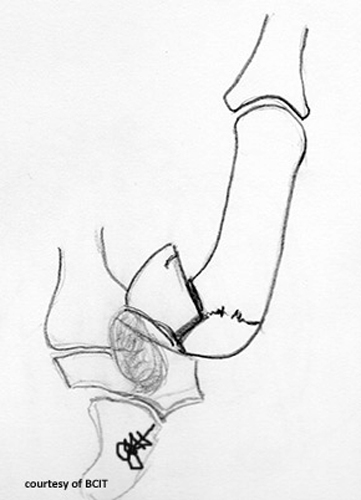

What does a 'spilled teacup' appearance indicate on lateral wrist imaging?

Lunate dislocation.

What causes lunate dislocation and what are its features?

FOOSH injury; volar displacement, loss of articulation with capitate and radius.

What is the treatment and complication of lunate dislocation?

Reduction, immobilization, often surgery; complications include arthritis and wrist instability.